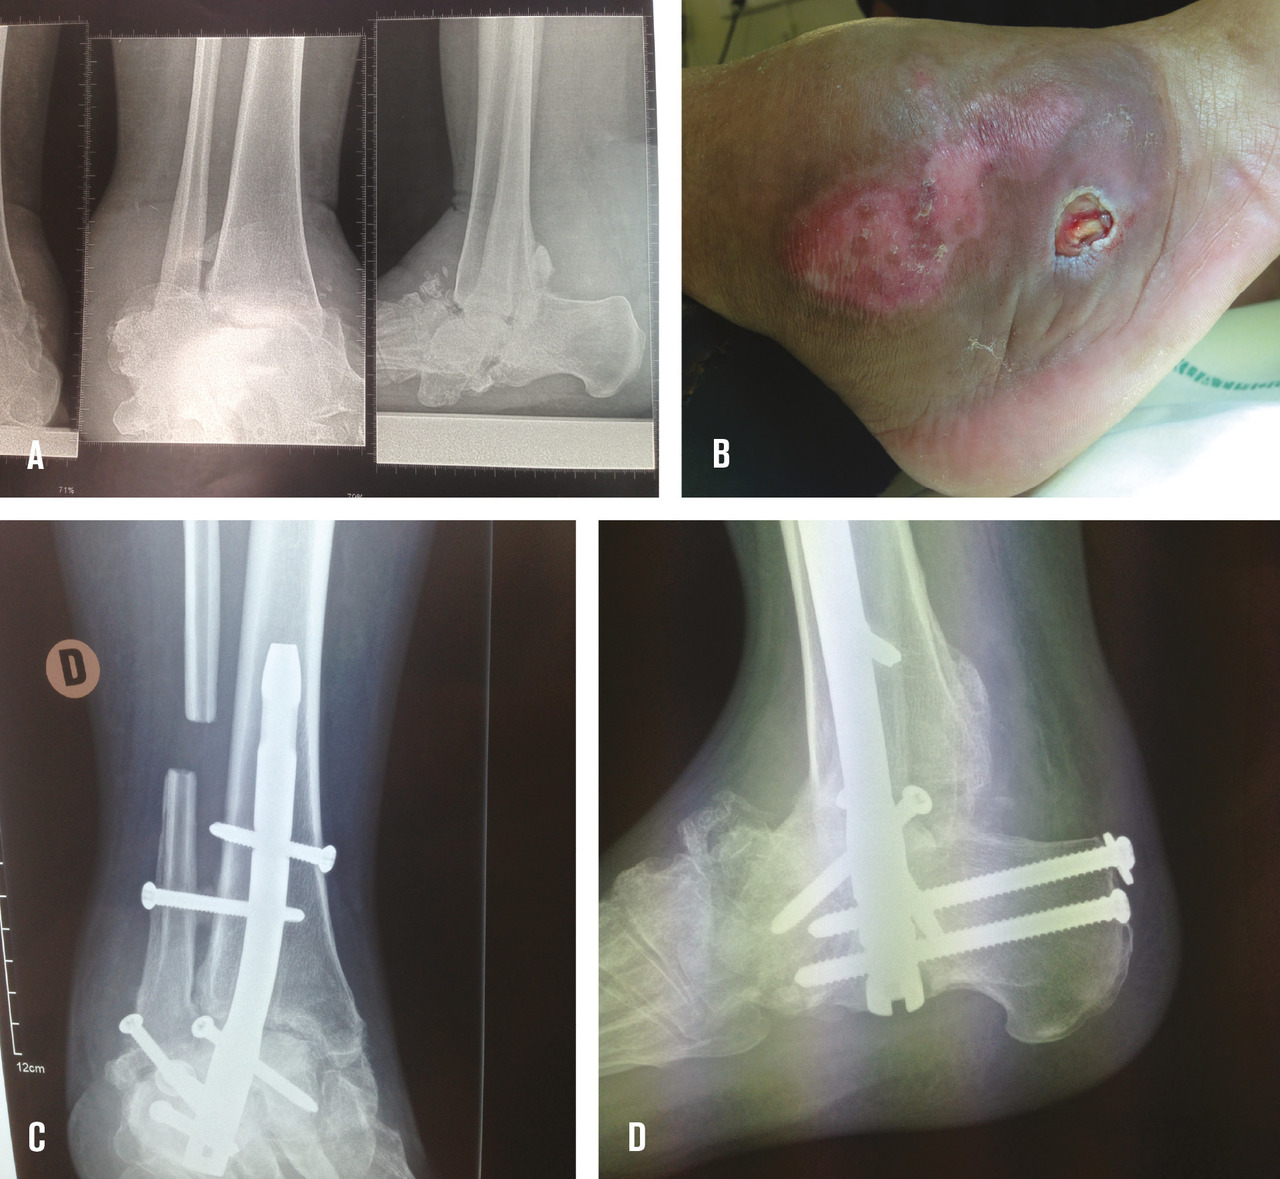

Les infections osseuses peuvent atteindre, dans le cas d’une ostéo-arthropathie de Charcot de la cheville, les malléoles ou le bord externe du pied, voire plus rarement entraîner une ostéo-arthrite tibio-talienne ou sous-talienne. Le traitement consiste là encore à débrider la plaie infectée et à exciser l’os infecté mais aussi à réaligner la cheville pour permettre la disparition de l’appui inadapté et permettre des appuis de meilleure qualité grâce à une pan-arthrodèse de l’arrière-pied dont l’ostéosynthèse par clou transplantaire est la technique la plus utilisée (fig. 4 ).

Les infections osseuses peuvent atteindre, dans le cas d’une ostéo-arthropathie de Charcot de la cheville, les malléoles ou le bord externe du pied, voire plus rarement entraîner une ostéo-arthrite tibio-talienne ou sous-talienne. Le traitement consiste là encore à débrider la plaie infectée et à exciser l’os infecté mais aussi à réaligner la cheville pour permettre la disparition de l’appui inadapté et permettre des appuis de meilleure qualité grâce à une pan-arthrodèse de l’arrière-pied dont l’ostéosynthèse par clou transplantaire est la technique la plus utilisée (